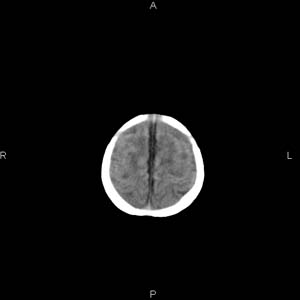

患者男,27天,出生后正常,今天中午在母亲怀里抱着吃奶在放下睡觉时发现后枕部慢慢出现一包块,来查头颅ct。无外伤史。包块内ct值47-51hu。请大家讨论。

支持脑膜脑膨出,双侧侧脑室三角区周围脑白质对称性低密度影,考虑缺血缺氧性脑病或肾上腺性脑白质营养不良。

\"中午在母亲怀里抱着吃奶在放下睡觉时发现后枕部慢慢出现一包块,包块内ct值47-51hu。

颅骨无缺损,骨缝无增宽.支持头皮血肿(血管破裂)